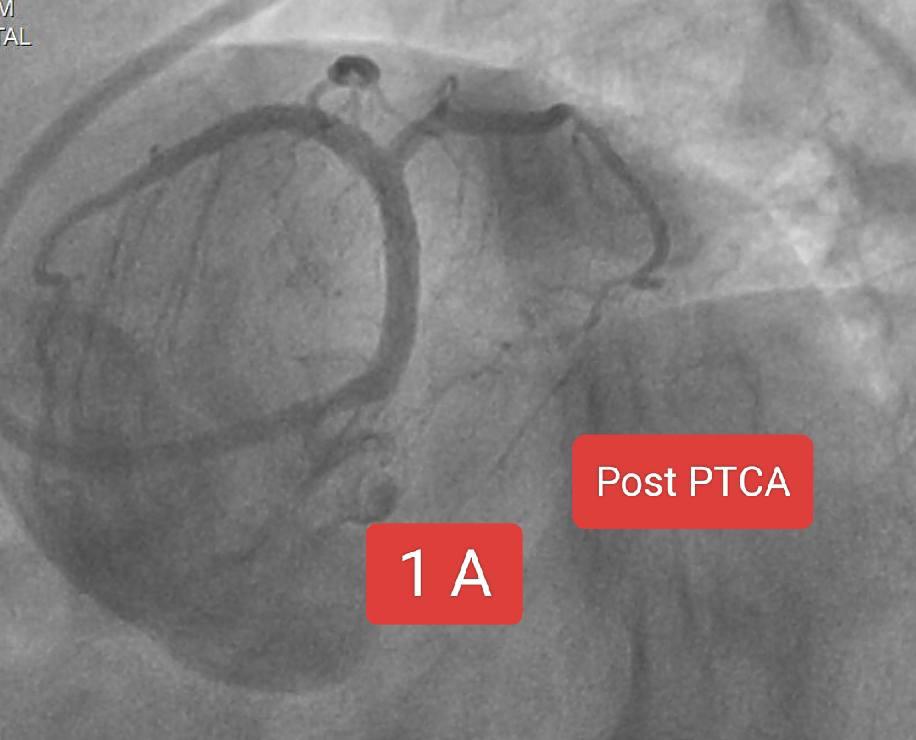

Two interesting cases of Left main stenting by mini crush technique done at Sunshine Hospital ,Bhubaneswar last month. Case 1 A 65 Years old Male Risk factors : Smoking, Hypertension Presented with Chest pain since 2 days ECG : Anterior wall STEMI ECHO : RWMA LAD Territory, LVEF 38% CAG : Left main + LAD + LCx disease PTCA done : Left main bifurcation stenting by Mini crush technique Case 1B 72 year old Male Risk factor : Smoking CAD Post PTCA status to OSTIOPROXIMAL LAD - D1 ( Bifurcation) ( 2020) Medications discontinued since 2022. ECG : aVR ST elevation ECHO : RWMA LAD Territory, LVEF : 45% CAG : Distal LMCA 95%, ostial LAD stent ISR 95% , ostial LCx 99% Patient refused CABG PTCA done : Left main bifurcation stenting by Mini crush technique Thanks to our cath lab team ( Sarfaraj Ahammed , Amit Gourav Bagh , Madhu Smita Swain , Anjan Jagannath Dash, Sanjib, Mami didi, Sameer and Raju) and Sunshine Hospital Bhubaneswar